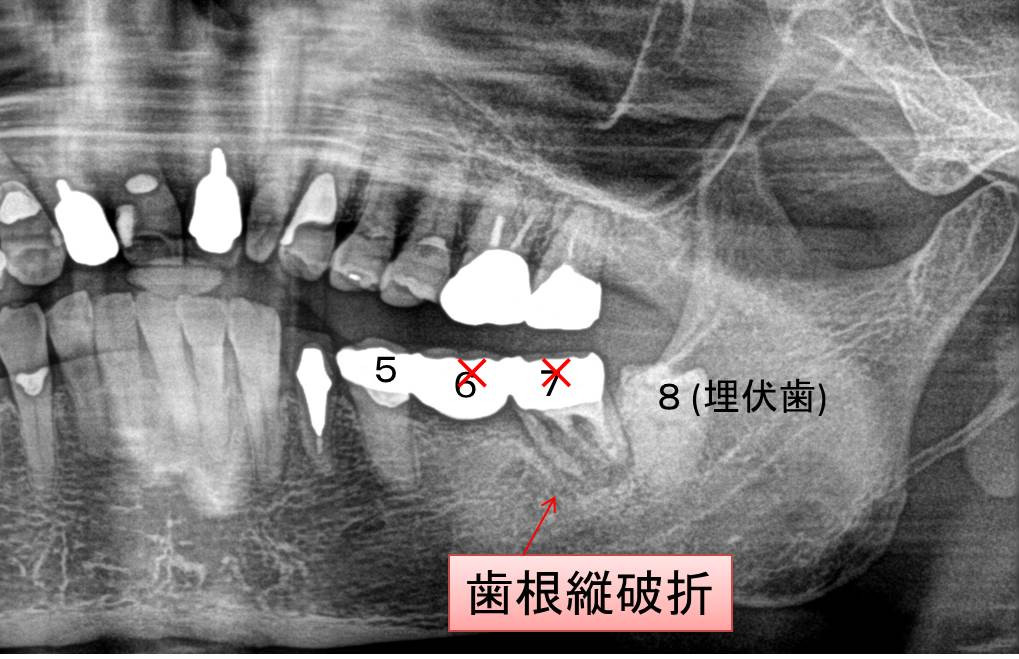

現在受けている治療に関する相談・セカンドオピニオンで来院される患者様が増えてきています。画像は奥歯にブリッジを装着する治療を最近受けた患者様のパノラマレントゲン写真の一部抜粋、改変したものです。2本の奥歯を支えにしたセラミックスによる3歯ブリッジですが、奥の歯が真っ二つに割れているのが分かります。「歯根縦破折を伴う慢性根尖性歯周炎」の診断により、抜歯適応であることを説明致しました。通院中の歯科担当医に診療情報提供を行ない、治療方針の再検討を提案させていただきました

奥歯が抜歯になった場合、代替治療法は義歯となることが多く、患者様のQOLに大きく影響することが考えられます。非常に難しい判断が必要だと思われます。